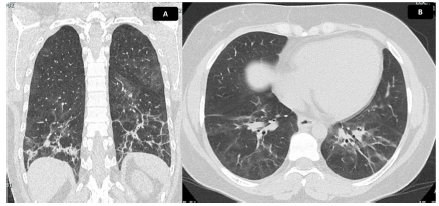

En abril del 2021 la paciente recibió la segunda dosis de ciclofosfamida sin que presentara complicaciones. Se realizó un control de pruebas de función pulmonar (PFP) que evidenció una capacidad de difusión de monóxido de carbono ajustada a la altura, moderadamente disminuida, con valor del 60%. La espirometría reportó una CVF del 69%, un VEF1 del 68% y una relación VEF1/CVF de 86. Se indicó continuar el mismo tratamiento, con seguimiento clínico mensual, sin embargo, por trámites administrativos con su aseguradora, asistió a control hasta junio del 2021, sin tratamiento farmacológico desde mayo de ese mismo anno. Refería además deterioro de tos y disnea 20 días antes de la consulta, asociado con fiebre, mialgias, astenia y adinamia. Se documentó caída importante de la SatO2, además de sinovitis y FR, por lo que se hospitalizó para descartar proceso infeccioso activo. Se tomaron hemocultivos y urocultivo; con reportes negativos; se llevaron a cabo pruebas moleculares para SARS-CoV-2, con reportes negativos, además de baciloscopias negativas y un nuevo control de tomografía de tórax (fig. 5), en el que se documentó progresión de EPI. Se consideró sintomatología secundaria a reactivación de SAS, por lo que se reinició prednisolona a dosis de 20 mg/día, se administró el tercer bolo de ciclofosfamida de forma intra-hospitalaria y se dio egreso con orden del cuarto bolo de ciclofosfamida. Luego de esta cuarta dosis, la evolución fue estacionaria por lo que se indicó control de PFP y TACAR luego de completar esquema de tratamiento por 6 meses con ciclofosfamida para determinar necesidad de inicio de rituximab.

Figura 5 Tomografía de tórax con hallazgos de EPI. Tomografía de tórax en corte coronal (A) y axial (B). Se evidencia vidrio esmerilado de distribución peribroncovascular, con mayor afectación de segmentos posteriores y lóbulos inferiores, donde se identifican reticulación, bandas parenquimatosas, engrosamiento de paredes bronquiales y bronquiectasias de tracción con pérdida de volumen asociada, debido a retracción de cisuras. Hallazgos compatibles con patrón de NINE fibrótica. Extensión calculada del 30%.